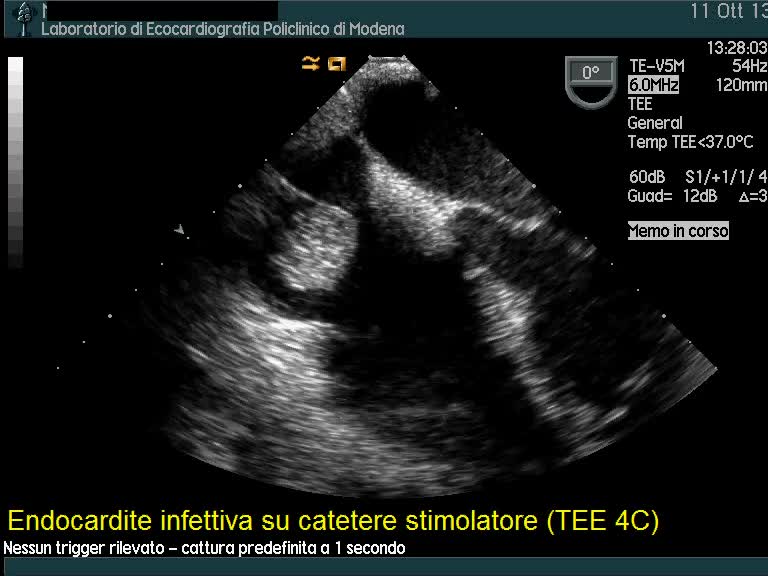

Endocardite infettiva su elettrocatetere stimolatore

Andrea Barbieri